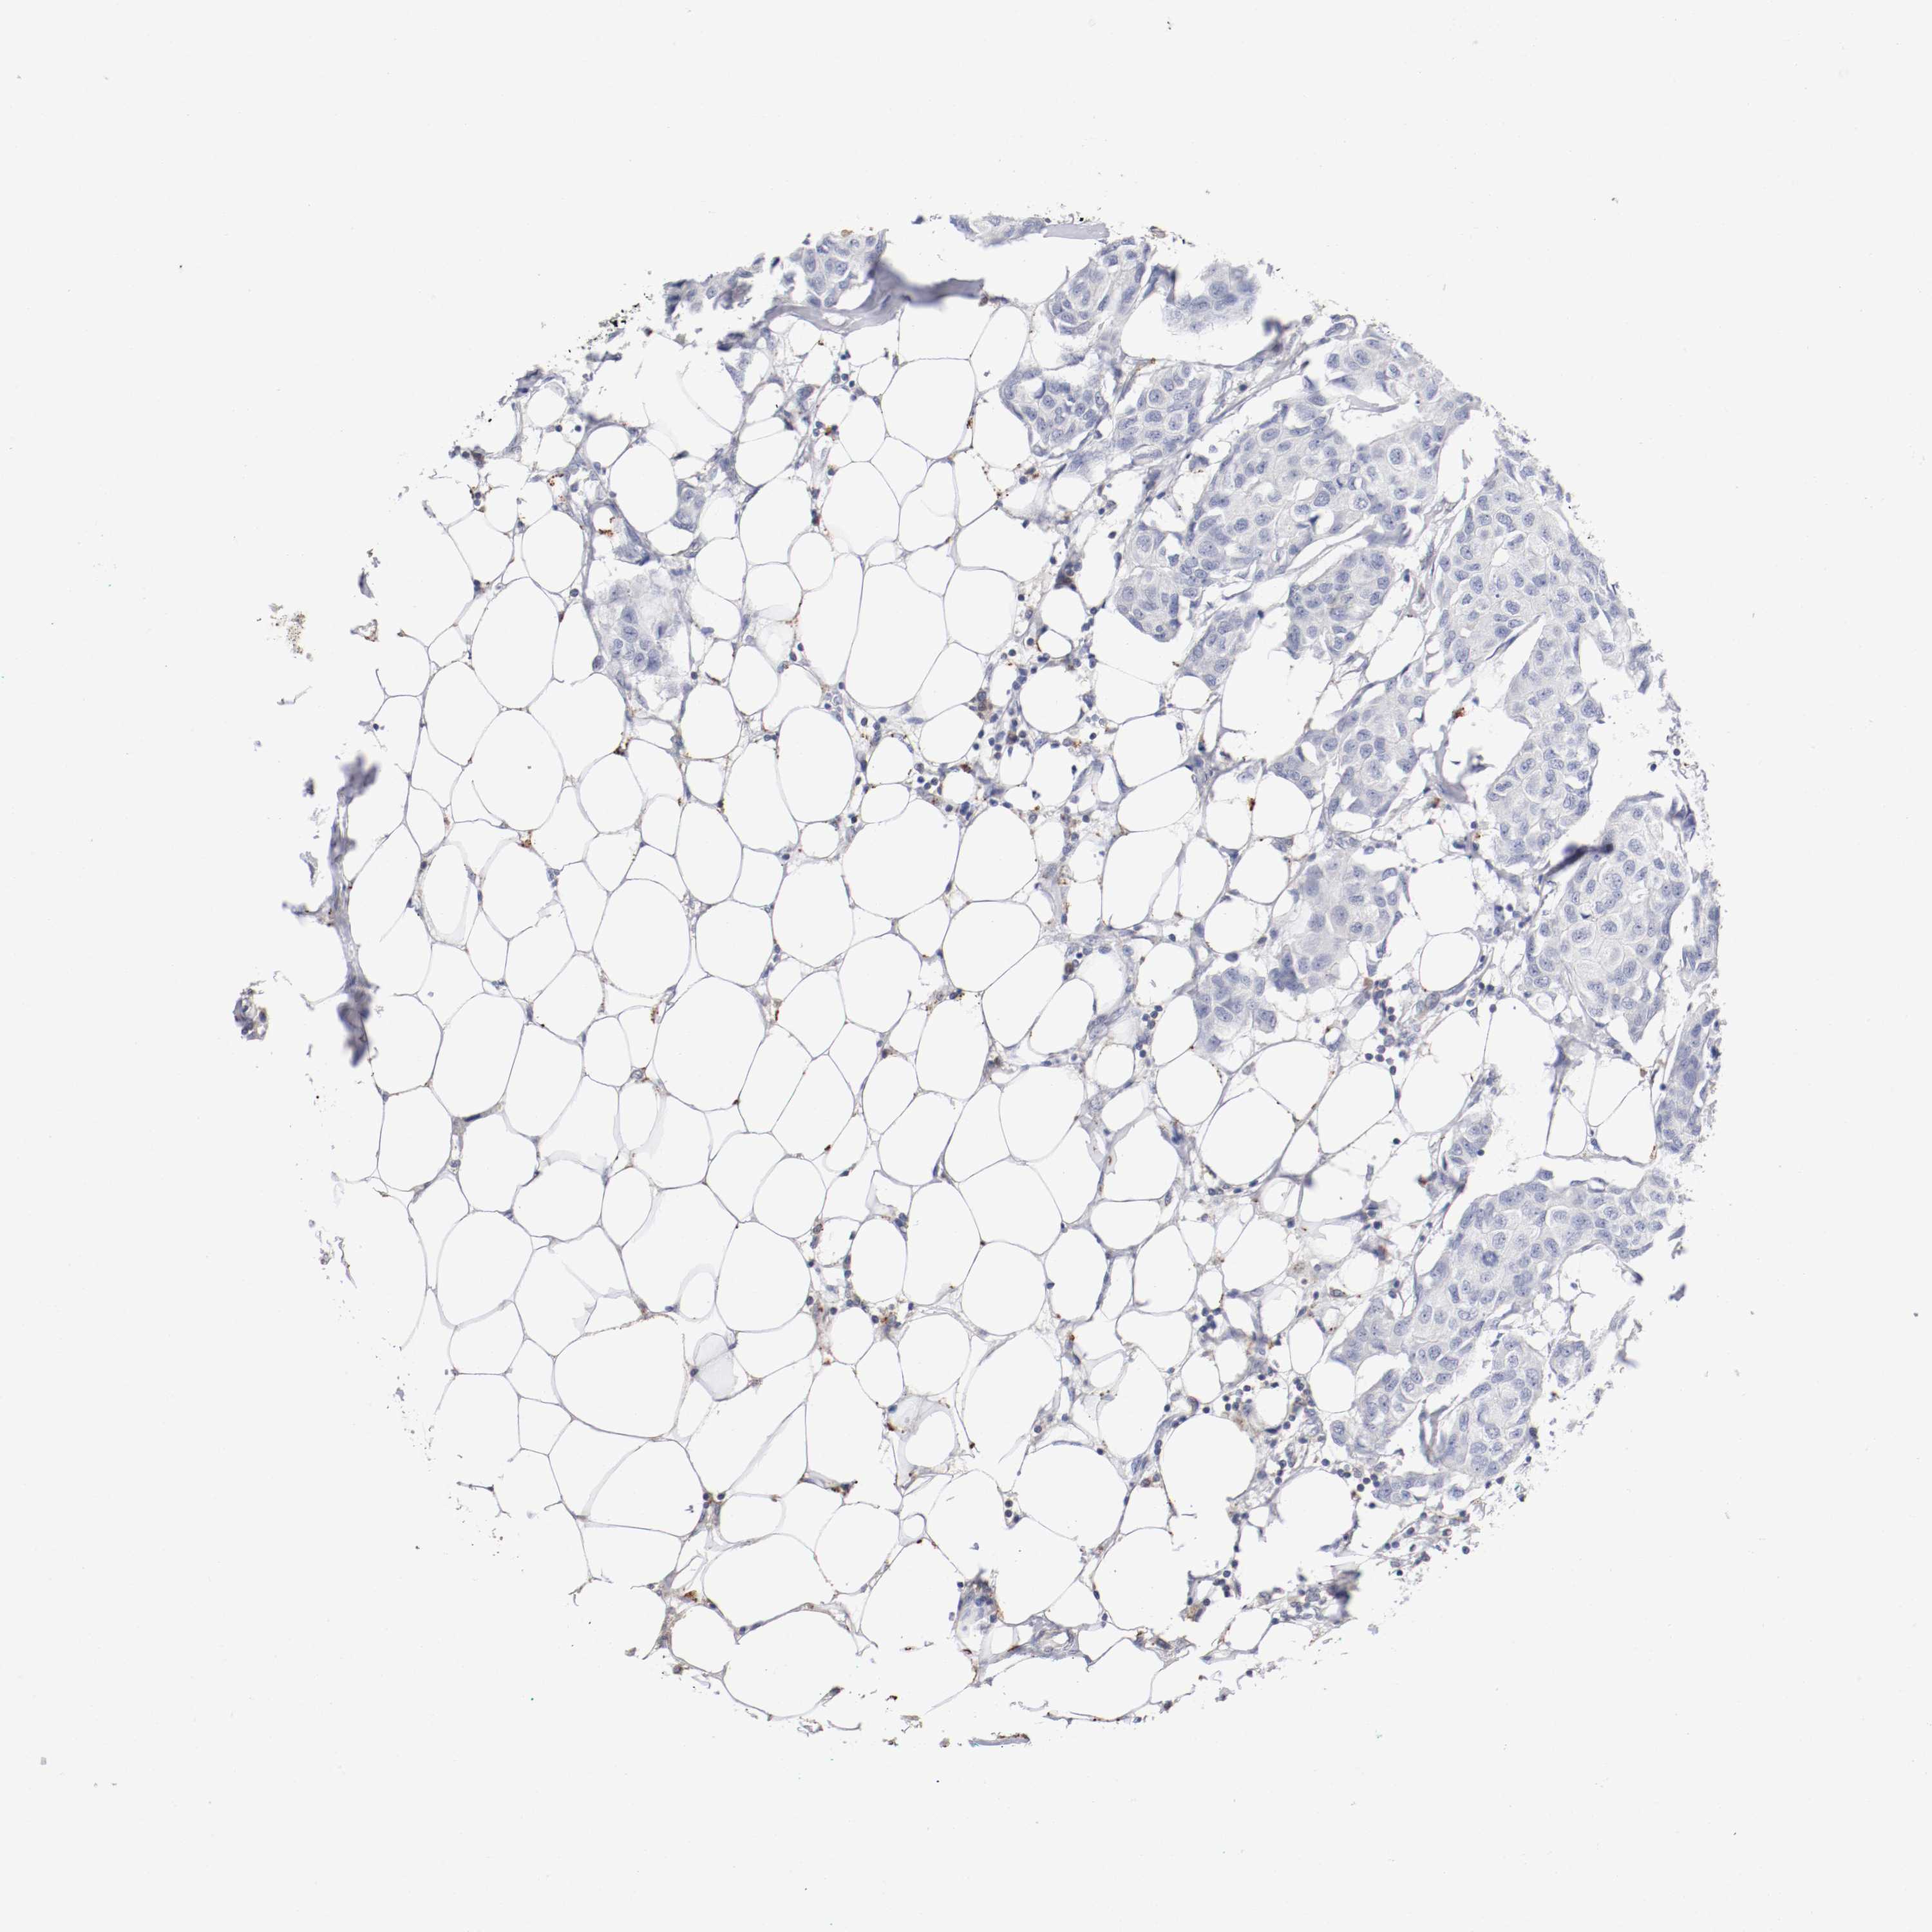

BRCA TCGA BRCA VALIDATION PROTEIN EXPRESSION

Breast cancer

Human cancer